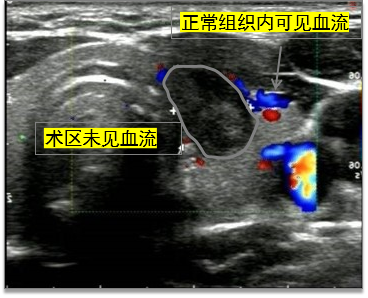

▲王女士在接受消融术后1月,超声显示甲状腺结节较前缩小,结节内未见血流信号。